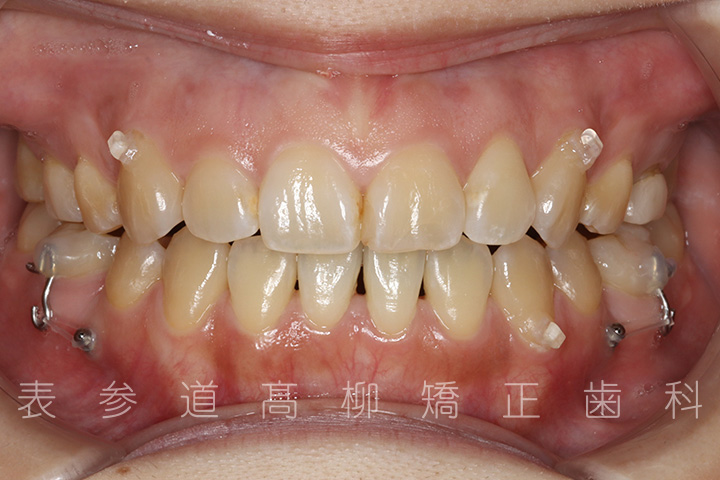

前歯のガタガタ感と開咬でお悩みの患者様の症例をご紹介いたします。

治療前→治療後

術前術後の比較